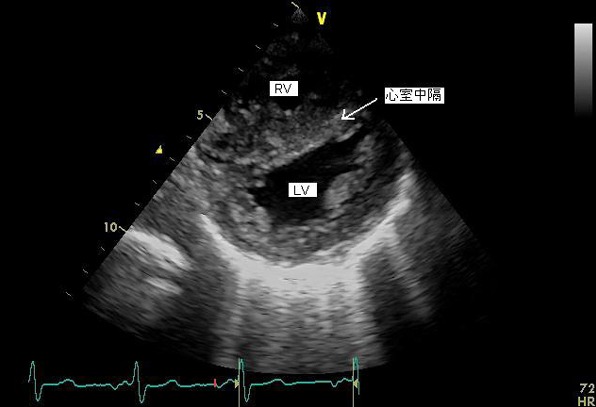

心エコー検査で(1)右室肥大(2)高位心室中隔欠損症(3)大動脈弁騎乗(4)右室流出路狭窄(肺動脈狭窄)を認めたことから、ファロー四徴症と診断された。

図1: 心エコー、左室、右室短軸像、肥大し圧が高くなった右室により、心室中隔は左室側に偏位している。